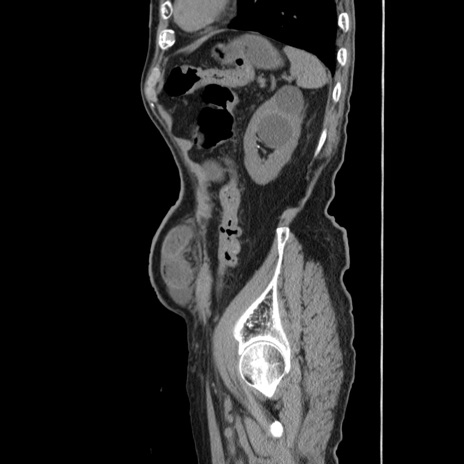

症例24(矢状断像)

【症例】80歳代男性

【主訴】左側腹部痛、嘔吐

【現病歴】本日早朝より左腹部に痛みあり。昼頃嘔吐認めたため、救急要請。

【既往歴】直腸癌(Mile手術)、胆摘

【身体所見】意識清明、BT 35.9℃、BP 221/93mmHg、SpO2 97%(RA) 、腹部:左ストーマ周囲に限局性の腹部膨隆あり。 膨隆部自発痛・圧痛あり・軟。

【データ】WBC 7700、CRP 0.09